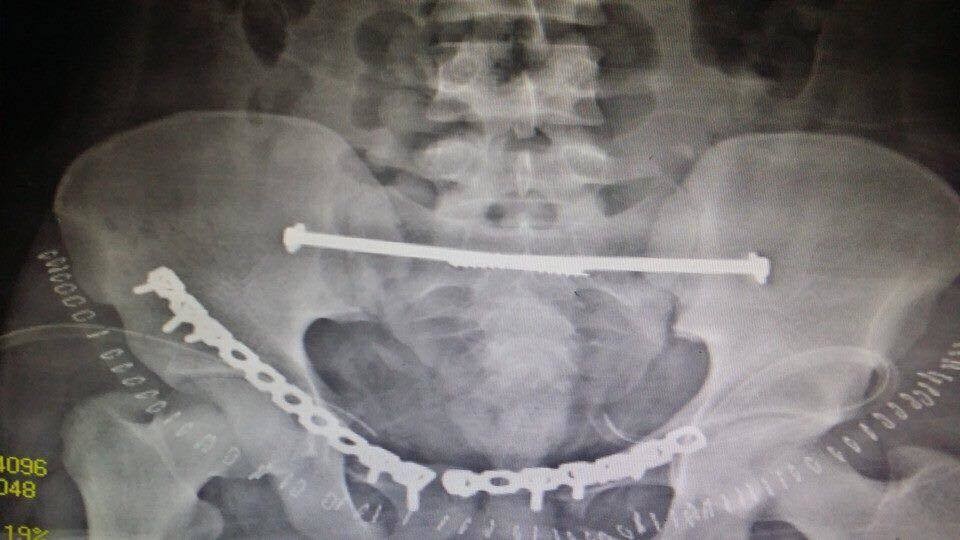

انقاذ مريض تعرض لكسور متعددة

انقاذ مريض تعرض لكسور متعددة بالحوض

المستشفي السعودي الالماني بالرياض يواصل اجراء جراحات الحوض المعقده بنجاح لافت

يواصل المستشفي السعودي الالماني بالرياض اجراء جراحات الحوص المعقدة بنجاح كبير ، جعله من المقاصد الطبية المتميزة ،تعد جراحات الحوض من الجراحات المعقده ، التى تعتبر تحديا كبيرا يواجه جراحى العظام، حيث تتطلب مجهودا كبيرا ومهارة من جراح العظام والفريق الطبى المعاون له . وتعتبر المستشفى السعودى الالمانى بالرياض احد المستشفيات الرائدة ذات السمعة الطيبه فى هذا النوع من الجراحات خاصه وفى جراحه العظام بصوره عامه.

وكان قد حضر مريض سعودى الى طوارىء المستشفى اثر تعرضه لحادث سياره ،وكانت حالته العامه صعبه للغايه . وعلى الفور تم عمل الإسعافات اللازمه للمريض وتم دخوله على الفور للعناية المركزه و عمل جميع الفحوصات اللازمه من اشعات عاديه وتليفزيونية ومقطعيه ، حيث تبين وجود كسور متعدده وانفتاح فى الحوض مع وجود نزيف حاد بالحوض قد يؤثر على حياه المريض . وعلى الفور تم إيقاف النزيف بواسطه فريق متكامل من أطباء الاشعه التداخليه.

وبعد استقرار الحاله العامه للمريض ، تمت مناظره الكسور الموجودة من قبل الدكتور محمد فوزي رئيس قسم العظام ، والذى قرر بإجراء تدخل جراحى لفتح وتثبيت الكسور المتعددة بالحوض بواسطه شرائح ومسامير معينه .

وبالفعل تم عمل التحاليل اللازمه ، و دخول المريض لغرفه العمليات ، حيث تم فتح وتثبيت الكسور . وبحمد الله وتوفيقه تمت العمليات جميعها بالحوض فى جلسه واحده وبنجاح تام ومكث المريض بالمستشفى لعده ايام بعد الجراحة للاطمئنان على الحاله العامه والغيار المستمر على الجروح . وبحمد الله خرج المريض من المستشفى بحاله جيده واستمر فى المتابعة بالعياده الخارجيه بقسم العظام بالمستشفى حتى تمكن من المشى بصوره منتظمة وطبيعية .